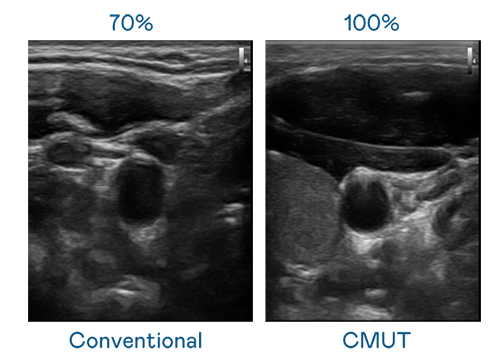

CMUT 技术是一种用电容式微机电元件来产生超音波讯号的技术。与传统 PZT 压电式技术相比,CMUT 频宽增加 30%,更宽频的超音波讯号让影像解析度大幅提升,是实现高影像品质医疗超音波扫描、促进精准医疗发展的关键技术。

大频宽带来超清晰影像

超音波影像的解析度高低,首先取决于探头能发出的讯号频宽。六合联盟 CMUT 可提供高清晰的超音波讯号,提供高频宽、高灵敏度、影像纹理细节更高的超音波影像,协助医护人员缩短影像判读时间及利用精准的医疗影像进行诊断。